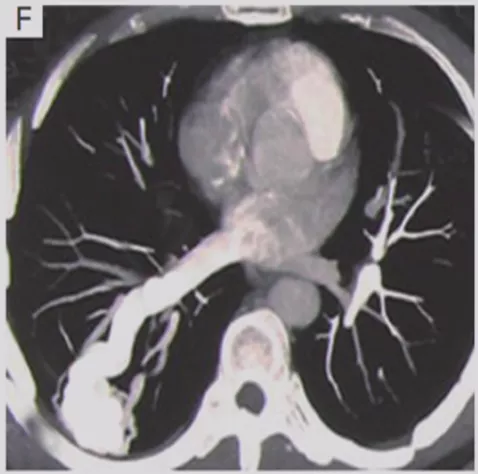

动静脉畸形

还有一点要提醒大家的就是血管畸形。多表现为圆形或轻度分叶的致密影,多位于肺门附近的肺内带,增强扫描时病变区强化明显供应动脉及引流静脉更加清晰。所以现在有的病人发现了结节,还是有必要做增强CT,为什么?如果你觉得这个结节没做过增强CT,靠活检、胸腔穿刺或者导航,如果病人是血管畸形,那必然会大出血,要面临很严重的并发症。所以对于结节病人,如果你采用介入性的或者是侵入性的诊断方法时,需谨慎一些,为了防止活检大出血,最好做个增强CT以观察。